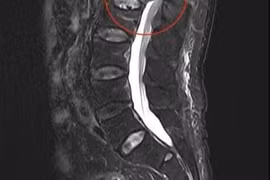

Bệnh nhân nữ, 60 tuổi, có tiền sử đái tháo đường và tăng huyết áp, được theo dõi định kỳ tại Bệnh viện Đa khoa Gia Đình. Trong quá trình tầm soát bằng CT phổi liều thấp, các bác sĩ phát hiện một nốt tổn thương nhỏ (kích thước 13 x 14 x 7 mm) tại phân thuỳ S7, thuỳ dưới phổi phải.

Qua theo dõi sát sao, tổn thương không thoái lui mà có các dấu hiệu nghi ngờ ác tính như: bờ không đều, tua gai, co kéo rãnh liên thuỳ và ngấm thuốc nhẹ sau tiêm cản quang.